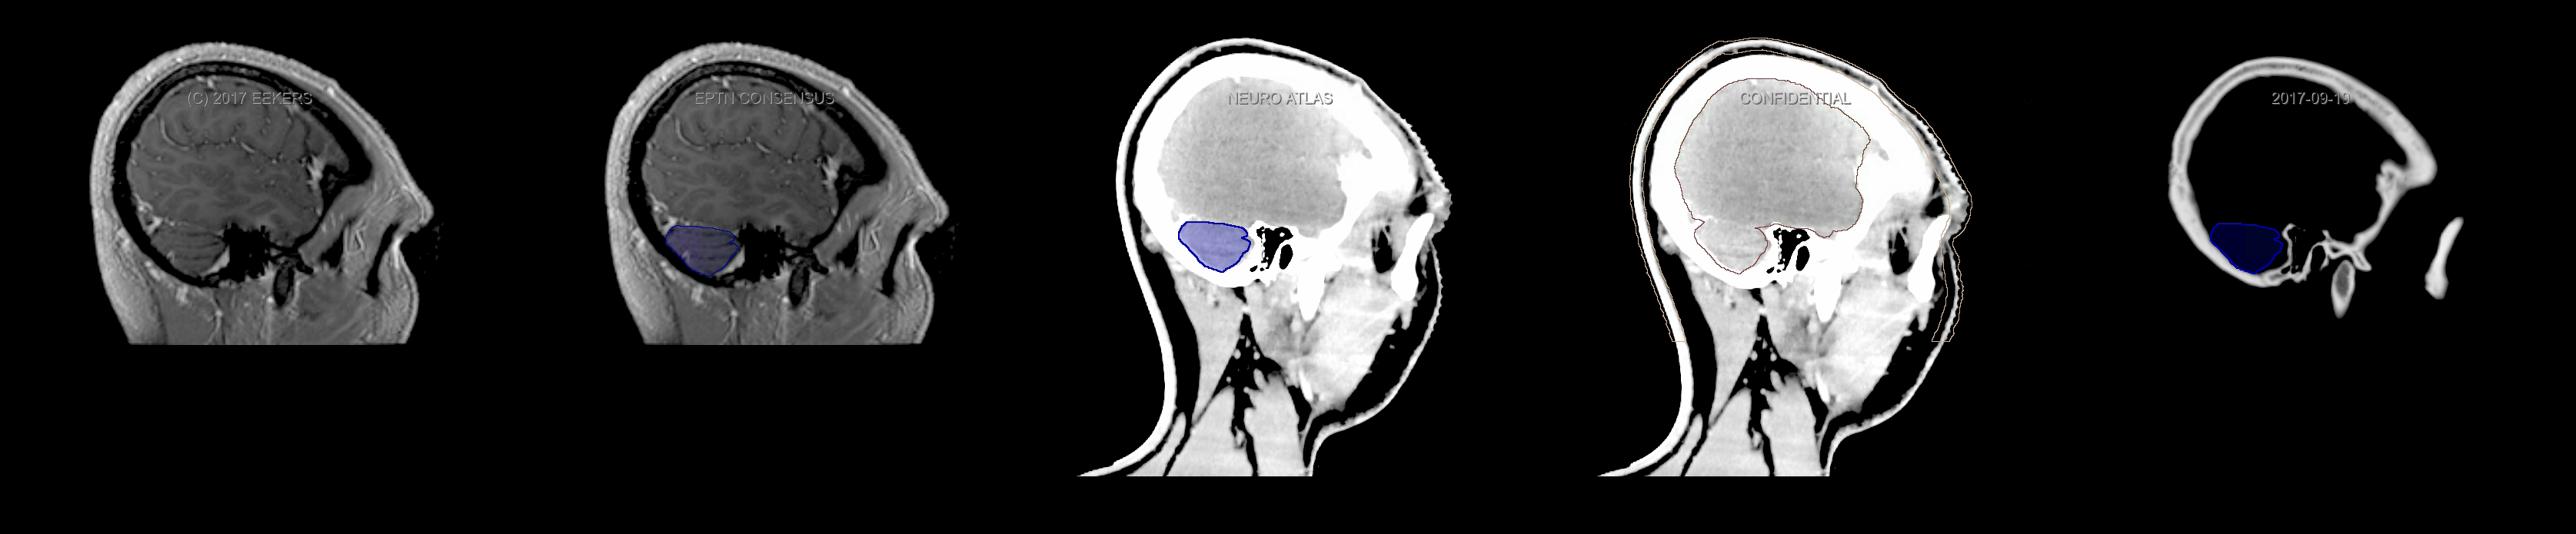

Eekers et al. have published an international neurological atlas for contouring of organs at risk in consensus with the European Particle Therapy Network (EPTN). The purpose of this consensus atlas is to decrease inter- and intra-observer variability in delineating OARs relevant for neuro-oncology. We propose this atlas is used in photon and particle therapy in order to derive consistent dosimetric data. When required this atlas will be updated according to new insights.

Included are all OARs known to be relevant for radiation-induced toxicity in neuro-oncology: brain, brainstem, cochlea, vestibulum & semicircular canals, cornea, lens, retina, lacrimal gland, optic nerve, chiasm, pituitary, hippocampus and skin. A new OAR relevant for neuro-cognition, the posterior cerebellum is also included.

Three-dimensional delineation of the fifteen consensus OARs for neuro-oncology are shown on CT and 3 Tesla (3T) MR images (slice thickness 1 mm with intravenous contrast agent). All are presented in transversal, sagittal and coronal view.

From left to right: MR without structures, MR with structures, CT (WW/WL 120/40) with structures, CT (WW/WL 120/40) with Brain and Brainstem Surface, CT (WW/WL 1500/120)with structures